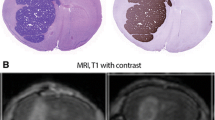

Comparison with Peripheral Metastases

To further investigate the role of the BTB in limiting lapatinib distribution, 14C-lapatinib concentrations were determined in systemic metastases and compared to those from the same animal in brain. The concept was that if one compared drug accumulation in two metastases from the same tumor cell line, one residing in the nervous system with a vascular barrier and one in systemic tissues without a vascular barrier, this may provide insight as to the function of the barrier system in limiting drug accumulation to CNS metastases. Twelve soft tissue metastases were found in peripheral tissues in the 12 h 14C-lapatinib animals; most (75%) were in the lung. Figure 3 presents representative images from one animal with a lung metastasis. 14C-Lapatinib concentrations were markedly greater in lung metastasis (3,464 ng/g) and surrounding normal lung tissue (20,784 ng/g) (Fig. 3) than those observed in matching brain metastases (454 ng/g). On average, brain metastasis14C-lapatinib concentration was only ~11% of that in lung metastases (Table I; Fig. 4). The ratio was even lower against many high uptake tissues, such as liver, kidney, and lung (Fig. 4). Only in a subset of brain metastases (17.5%) did lapatinib concentrations (~1,698 ng/g) approach those of peripheral metastases (2,549–3,889 ng/g) (Fig. 4). The markedly lower 14C-lapatinib concentration in most brain metastases as compared to matching metastases in systemic tissues provides additional support for the hypothesis that the BTB plays a significant role in limiting lapatinib distribution to metastases in the CNS.

14C-Lapatinib in lung (a–d) metastases at 12 h after 14C-lapatinib administration (100 mg/kg, oral). Representative sections showing lung metastasis EGFP fluorescence (a), Texas Red 3 kDa dextran fluorescence (b), cresyl violet staining (c) and 14C-autoradiography (d) from an animal with 231-BR-HER2 metastases that received 14C-lapatinib at 12 h prior to euthanasia. Matching metastases were also measured in brain from the same animal.

14C-Lapatinib concentrations in brain and peripheral metastases, as well as blood and other tissues, at 12 h after 14C-lapatinib administration (100 mg/kg, oral) in immunocompromised mice with 231-BR-HER2 metastases. Bars represent mean ± SD for n = 5 animals. Lapatinib concentration (y-axis) is shown in log scale. Points represent concentrations in individual metastases; mean concentration is shown by a line.